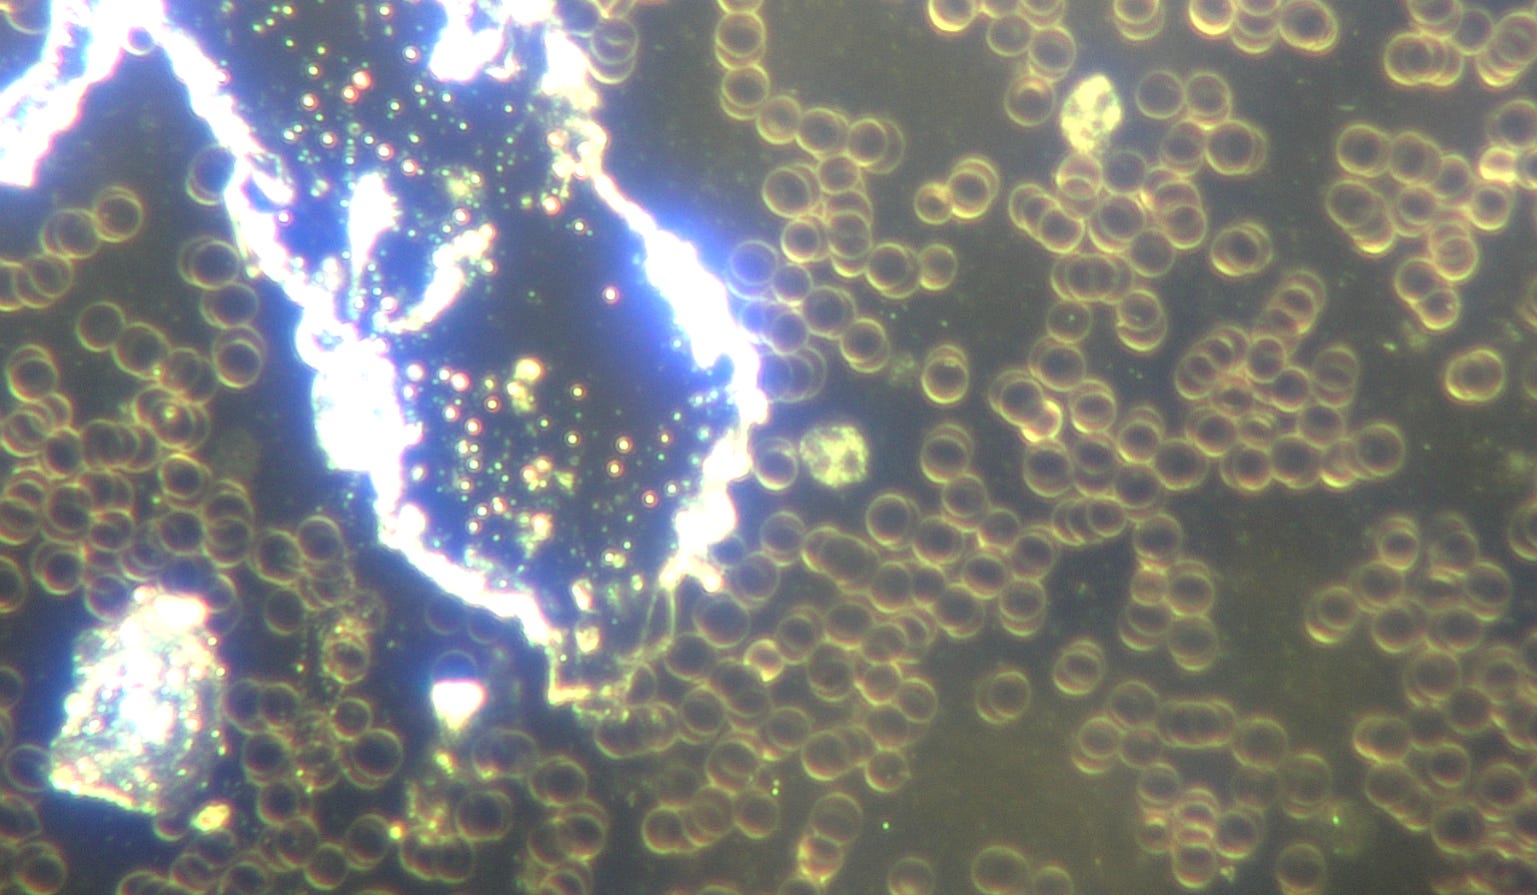

Son analyse sanguine après 4 jours de traitement a montré une nette amélioration. Il est impossible d'obtenir un échantillon sanguin parfait et des anomalies peuvent toujours être observées sur la lame. Je recherche désormais une quantification globale des micropuces et filaments polymères, des quantités totales de microrobots et de la qualité cellulaire comme indicateur d'amélioration, en parallèle avec d'autres résultats objectifs, tels que l'amélioration des marqueurs inflammatoires en laboratoire, de la fonction rénale, l'augmentation de la tension cérébrale lors des tests du système nerveux autonome et de l'EEG fonctionnel, ainsi que l'amélioration des symptômes cliniques.

Analyse sanguine en champ sombre (jour 4 du traitement) : amélioration de la qualité du sang et réduction significative des anomalies microtechnologiques. Grossissement : 200x. © Dr Ana Mihalcea

Je vérifie systématiquement la résistance de la membrane cellulaire et la présence de reflets dorés à l'intérieur de la cellule, signes de restauration de sa capacité électromagnétique, ainsi que la dissolution des rouleaux. Aucun filament polymère ni microprocesseur n'a été observé.

Analyse sanguine en fond noir (jour 4 du traitement) : amélioration des paramètres sanguins. Grossissement : 2000x. © Dr Ana Mihalcea